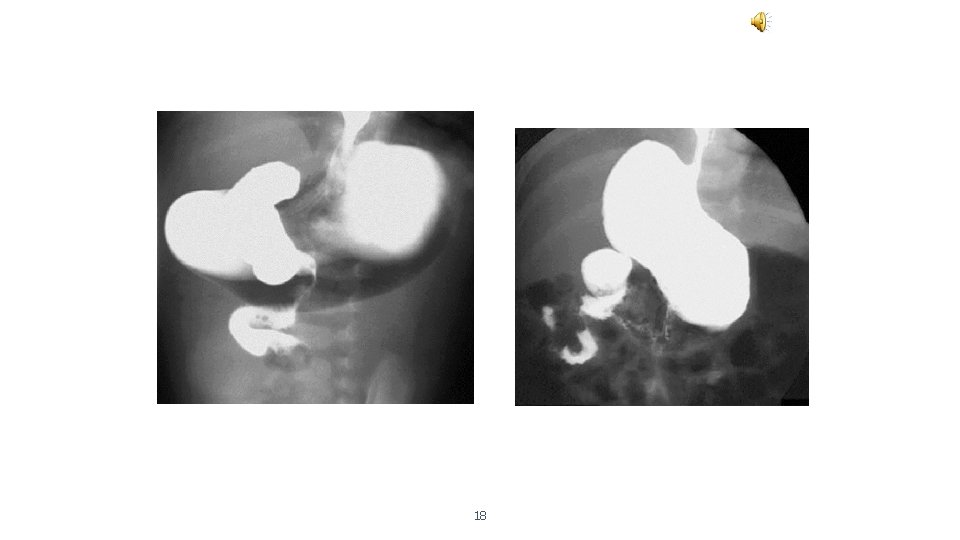

Orta Bağırsak Volvulus - Tanı • Üst sindirim sistemini değerlendiren opaklı radyogramlarda mide ve duedonumun dilate olduğu ve opak maddenin jejunuma geçmemesi veya çok az geçmesi • Tirbüşon • Gaga görüntüsü • Baryumlu kolon grafisi • Ancak nonrotasyonda çekum sağ alta olabilir

18